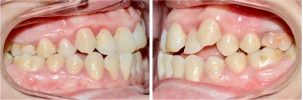

CAS 3 : Orthodontie de l’enfant - Syndrome de Brodie - Croissance des mâchoires

Cette patiente présente un Syndrome de Brodie qui se caractérise par un maxillaire (mâchoire du haut) trop grand par rapport à la mandibule (mâchoire du bas). Cela a pour conséquence d’entrainer une exoclusion (dents du haut trop à l’extérieur pour toucher les dents du bas) du secteur latéral droit.

Le traitement a consisté en un alignement dentaire suivi d’une phase d’expansion de la mandibule (grâce à l’appareil), associée à une stimulation de la croissance de la mandibule (mâchoire du bas) à l’aide d’élastiques.

La stabilité du traitement a été assurée à l’aide de fils collés en haut et en bas ainsi que des gouttières de contention pour stabiliser la largeur des mâchoires.